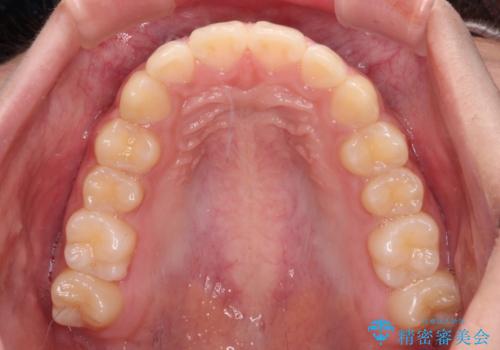

ワイヤー装置と補助装置を有効に活用し、さらには高校生ということもあり、1年9か月で狙い通りの仕上がりを達成することができました。